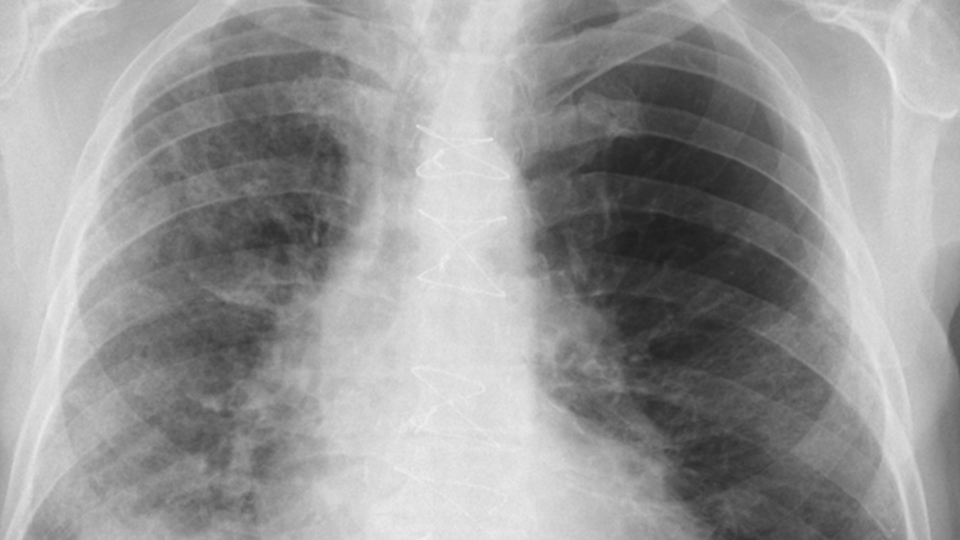

Das neuartige Coronavirus legt das Leben immer noch weitgehend lahm. Doch die Medizin lernt täglich dazu. Mittels Computertomographie lassen sich heute Prognosen über den Verlauf einer durch COVID-19 ausgelösten Lungenentzündung erstellen.

SARS-CoV-2 legt das öffentliche Leben weiterhin lahm. Doch anders als am Beginn der Pandemie sind die Ärzte und Wissenschaftler nun besser auf die speziellen Anforderungen, die das Virus an die Medizin stellt, vorbereitet. Durch den gezielten Einsatz der Computertomografie (CT) unterstützt das Institut für Röntgendiagnostik des Universitätsklinikums Regensburg (UKR) die behandelnden Intensivmediziner und kann anhand der Bilder eine Prognose über den Schweregrad des vom Coronavirus SARS-CoV-2 ausgelösten Lungenentzündung (Pneumonie) erstellen. Denn die Radiologische Bildgebung kann pandemische Lungeninfektionen erkennen, bewerten, messen und nachverfolgen.

Während die erste Welle Politik, Bevölkerung und Mediziner gleichermaßen überraschte, hat sich seitdem gerade das Instrumentarium für die Diagnosestellung und Nachverfolgung einer COVID-19-Erkrankung rasant weiterentwickelt. Einen wichtigen Baustein dazu liefern die Computertomografie und die Röntgendiagnostik. „In der ersten Welle waren die PCR-Tests noch fehleranfällig und langsamer. Da sich die COVID-19-Pneumonie mit einem relativ typischen Bild in der Lunge äußert, konnten wir mit der Röntgenthoraxaufnahme und Computertomografie helfen, die Erkrankung schnell zu diagnostizieren und gleichzeitig das Ausmaß der Lungenbeteiligung zu bestimmen. Inzwischen sind die Tests drastisch verbessert, so dass sich die Aufgabe der Bildgebung verändert hat. Wir konzentrieren uns jetzt auf die schwerer erkrankten Patienten, da wir gelernt haben, wie wir mit der Bildgebung einen Beitrag zur Prognoseabschätzung leisten können. Zudem können wir Komplikationen wie eine Lungenembolie erkennen“, erklärt Professor Dr. Okka Hamer, Leiterin der Kardiopulmonalen Bildgebung des Instituts für Röntgendiagnostik des Universitätsklinikums Regensburg. Die Spezialisten des Instituts befassen sich schon seit Beginn der Pandemie intensiv mit dem gezielten Einsatz von Thorax-CT und Thorax-Röntgen. Auch der erste bundesweit komplett dokumentierte Fall wurde von Professor Hamer und ihrem Team publiziert. Dabei handelt es sich um die erste befundete Fallanleitung unter Berücksichtigung aller medizinischen Begleitumstände.

Erfahrungen aus China zeigten, dass auch bei einem negativen PCR-Test und bei typischen klinischen Symptomen die Thorax-CT schon im frühen Stadium einer COVID-19-Erkrankung pneumonische Verdichtungen zeigen kann, die suggestiv für eine COVID-19-Pneumonie sind. „Wir können einen entscheidenden Beitrag zum klinischen Management der Behandlung leisten“, sagt Professor Dr. Christian Stroszczynski, Direktor des Instituts für Röntgendiagnostik des UKR.“ Gerade die CT-Bildgebung hilft uns hier sehr. Durch neue Techniken können wir die Strahlendosis drastisch reduzieren, so dass die Belastung kaum größer ist als bei einer Röntgenthoraxaufnahme. Das UKR hat für die Befundung von COVID-19-Patienten eigens ein modernes Multislice CT von der Bayerischen Staatsregierung zugeteilt bekommen. „Dank diesem hochauflösenden CT können wir nun noch besser infektiöse und immunvermittelte Entzündungen in der Lunge erkennen“, so Professor Stroszczynski weiter.

Eine COVID-19-Pneumonie äußert sich häufig durch ein Mischbild aus sogenanntem Milchglas und Konsolidierungen in der Lunge. Zusätzlich kann, insbesondere in späteren Stadien der Erkrankung, ein „Crazy Paving“, eine durch glatt berandete Retikulationen überlagerte Milchglastrübung, auftreten. „Diese Verdichtungen finden sich bilateral und multifokal in den Mittel- und Unterfeldern der Lunge“, so Professor Hamer. „In Abgrenzung zu Pneumonien, die von anderen Erreger verursacht werden, fällt auf, dass die COVID-19-Pneumonie vor allem die Peripherie der Lunge befällt und zumindest anteilig scharf berandet ist, das ist ungewöhnlich.“